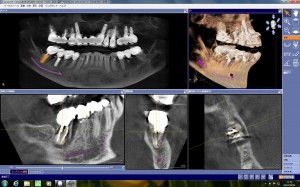

今日は、先天性欠損の右上犬歯部位にガイドサージェリーで、ストローマンボーンレベルインプラントのRC 4.1Φ10mmを埋入しました。

口蓋側の基底結節部にアクセスホールが来るように、埋入角度とポジションを正確に口腔内に埋入するために、セレッ…